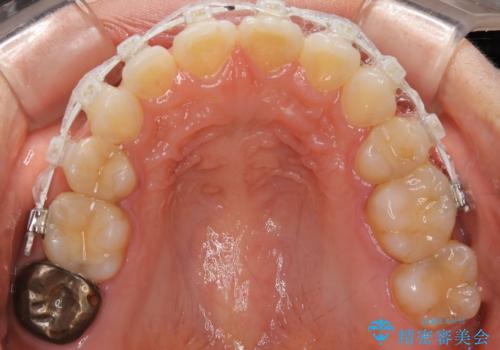

前歯のガタつきを改善 抜歯矯正後の後戻り

- 抜歯矯正後の後戻りで前歯ガタつきが主訴で来院された患者様です。

後戻り矯正や非抜歯矯正はインビザラインをご案内する事が多いですが、自己管理の煩わしさから、目立たないワイヤー装置にて矯正治療を行うこととしました。

後戻りの程度としては軽度なので、治療期間としては短く終えることが出来ました。

前歯の正中線も改善され大変満足して頂きました。